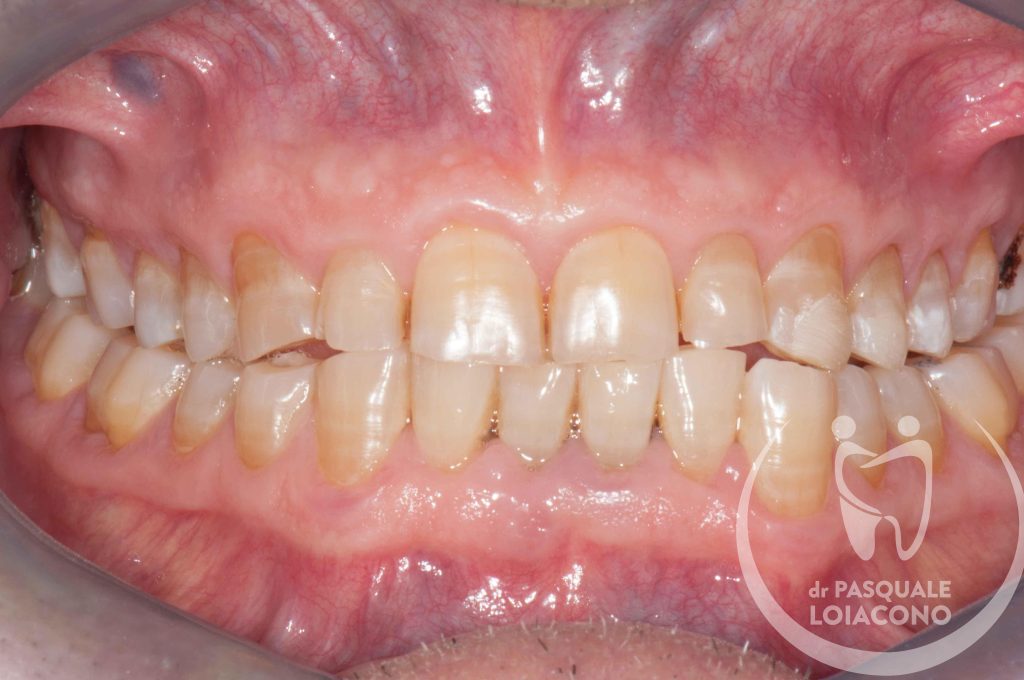

In generale nel funzionamento della bocca è preferibile che ci sia la simmetria tra le parti destra e sinistra, perché segno di equilibrio muscolare. Le asimmetrie delle arcate sono spesso la conseguenza di abitudini di masticazione prevalente su un solo lato, condizione non ottimale perché potrebbe creare tensioni nel nostro sistema posturale e sulle articolazioni della mandibola.

Quando ci sono problemi articolari della mandibola è necessario ricercare un’occlusione dentaria che rimetta il sistema il più possibile in equilibrio. L’organo della masticazione non è costituito solo da denti, ma anche da articolazioni e componenti neuromuscolari, e solo quando tuti i componenti sono in armonia tra loro si può avere salute e benessere. In realtà non tutti gli studiosi sono d’accordo su questioni fondamentali e non esiste visione unanime. Questo vuol dire che potreste incontrare un odontoiatra che sconsiglia qualsiasi trattamento, se non fisioterapia e massaggi o addirittura solo terapia psicologica di sostegno. All’opposto esistono scuole di pensiero che identificano nell’occlusione il fattore scatenante di una patologia che comunque resta complessa e multifattoriale. Da dentista desidero che la bocca funzioni bene e segua le regole stabilite, perché considero comunque positiva questa condizione, e quindi cerco di riportare l’occlusione del paziente verso una condizione il più possibile ideale.

Tuttavia il bite è una soluzione efficace ma temporanea: occorre ripristinare una chiusura (occlusione) dentale favorevole e armonica. Quindi occorre fare una diagnosi e una terapia assolutamente personalizzata e specifica.